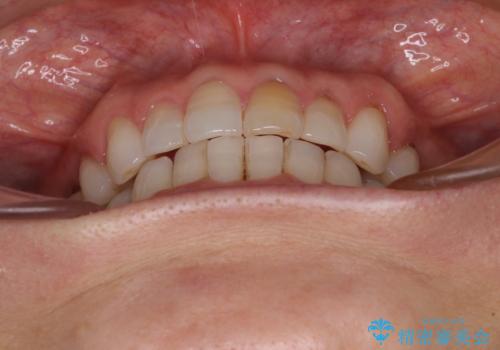

矯正治療の後戻り インビザライン・ライトでの再矯正

- 上下前歯を中心に、以前行った矯正治療の後戻りが気になるとのことで来院された患者様です。

後戻りは軽度であったため、インビザライン・ライトにて治療を行うこととしました。

矯正治療後は、再度後戻りすることを極力回避するために、下顎前歯の舌側を細いワイヤーを用いて保定することとしました。